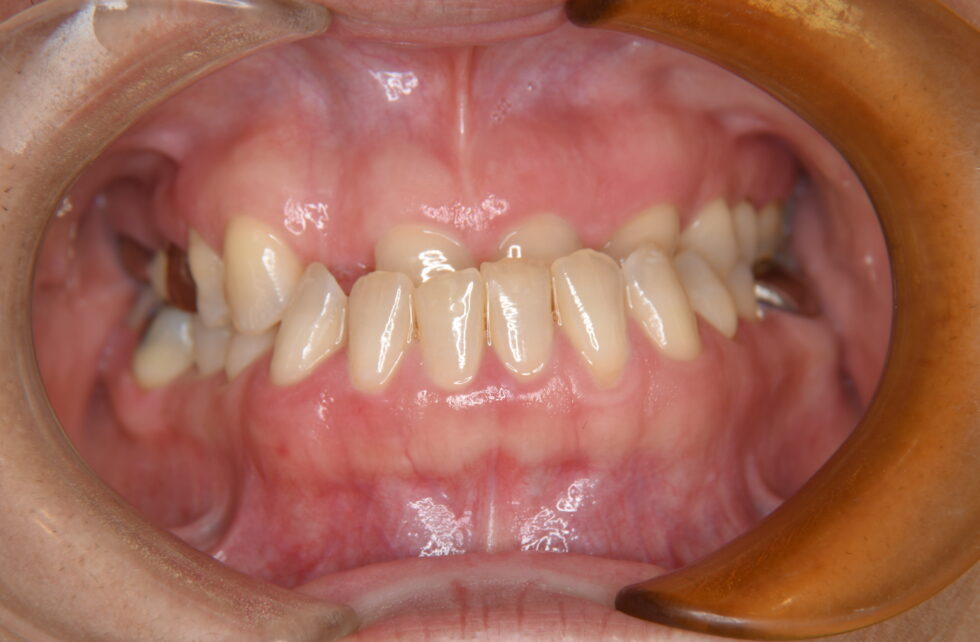

全ての前歯部が反対咬合となって、上顎左右側側切歯は先天欠損、上顎右側第一大臼歯は欠損してブリッジによる補綴処置が行われていた。セファログラム他の分析を行い骨格性反対咬合と診断した。矯正治療単独では被蓋の改善が十分行えないと評価し、顎離断術を併用した外科矯正を計画した。先天欠損である上顎側切歯部の空隙を閉鎖するように術前矯正を行い顎離断術を行った。手術後、術後矯正を行い保定へ移行した。前歯部の被蓋は改善し、上顎前歯の空隙の閉鎖が行われた。動的治療期間:術前、術後合わせ3年8カ月間

診察してもらえて病院での診断で顎変形症との事で矯正がSTARTしました。装置が付くまで私の歯に問題もありましたが何とか装置も付き、食事もしにくい生活はしんどかったですが、自分の歯が動いているのが嬉しかったです。R6年11月18日のSSROの手術も無事に終わり受け口が受け口ではなくなったし、歯並びもキレイになりました。

R7年10月3日には装置卒業できリテーナー装着になりました。